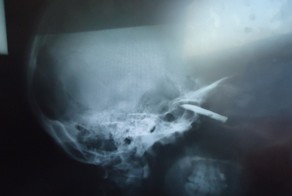

Боцман в очередной раз сказал свое заклинание "а якось воно будэ" и решительно запустил руку в рану. Пахомову показалось, что с кишками у него попутно выдирают и сердце. Внезапно боль унялась. Левая рука боцмана все еще утопала где-то в Пахомовском брюхе, а правая рука бережно, двумя пальчиками, вертикально держала весьма длинный багрово-синий червеобразный отросток. Брыжейки практически не было, все сосуды шли прямо по стенке аппендикса. К ране вплотную прижималась слепая кишка. Пахомов схватил лигатуру и попытался приподняться. Замполит поддерживал его под плечи. Напряжение брюшной стенки опять пробудило боль и Пахомов заговорил с подвыванием: "Щааас, я-ааа тебя-ааа, суку, апендюка, перевяжу!" Перевязал. Хорошо ли, плохо - сил нет переделывать. Уже лежа и глядя в зеркало перевязал еще раз. Потом окрасил йодом своего больного червяка и отсек его.

Замполит заорал "Есть операция!!!" и подставил банку с формалином. Отросток плюхнулся в банку, а культя и слепая кишка опять ушли в рану. "б.... Боцман достань опять, так что б обрубок мне был виден! Ушить надо!" Пытка повторилась снова и закончилась тем же - странно и совсем не по хирургически выкрутив руки боцман снова вытянул слепую кишку. Он сильно и больно давил на брюхо. Картина такой ассистенции совершенно не походила на то, что делали в клиниках. Слабеющей рукой Пахомов взял иглодержатель с кетгутом. "Только бы не проколоть кишку насквозь!" Он еще раз прижег культю отростка йодом и попытался подцепить иголкой наружный слой цекума. Выходило плохо. Иглодержатель перешел в руки кока. У того тоже выходило не лучше - кое где нить прорвала ткани, но местами держала. Попытались затянуть кисет. Получилось довольно некрасиво, но культя отростка утопилась. "Ладно, не на экзамене, сойдет и такая паутина. Вяжем." Узел Пахомов завязал сам. Показал как надо шить брюшину простейшим обвивным швом. На это дело пошел боцман, твердя свою мантру "а якось воно будэ, а шо - як матрас штопать!" Потом лавсаном ушили апоневроз. Узлы были несколько кривые, но фасция на удивление сошлась весьма ровно. Просто брюшная стенка была настолько перекачана новокаином, что ее Пахомов уже шил сам, практически не ощущая никакой боли. Сам он и закончил операцию, наложив швы на кожу. Швы, правда, тоже были далеко не мастерские - кое где выгладывали "рыбьи рты" от неправильно сошедшихся краев под узлом. Да плевать - лишь бы не разошлось, а уж уродливые рубцы на брюхе как-нибудь переживем.